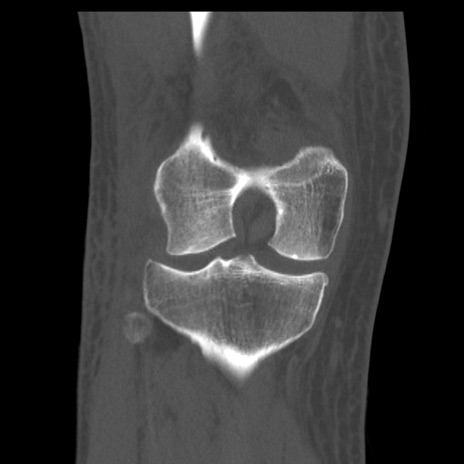

症例28 右膝関節CT(冠状断像)

右膝関節CT